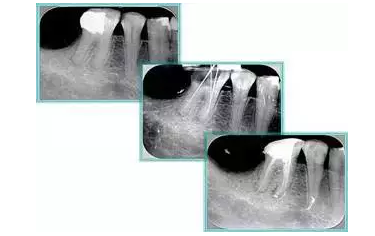

二、臺階

定義:根管內(nèi)壁上人為產(chǎn)生的不規(guī)則形狀阻止器械順利進(jìn)入根尖。

原因:器械沒有預(yù)彎,根向壓力過大。

右圖箭頭處示臺階形成。

解決方法: ( 1 )器械預(yù)彎。 ( 2 )若出現(xiàn)銼的螺紋擰緊,立即換用小號銼。 ( 3 )一旦到達(dá)WL,即按照從小到大順序預(yù)備根管。 ( 4 ) H銼幫助提高切割效率。